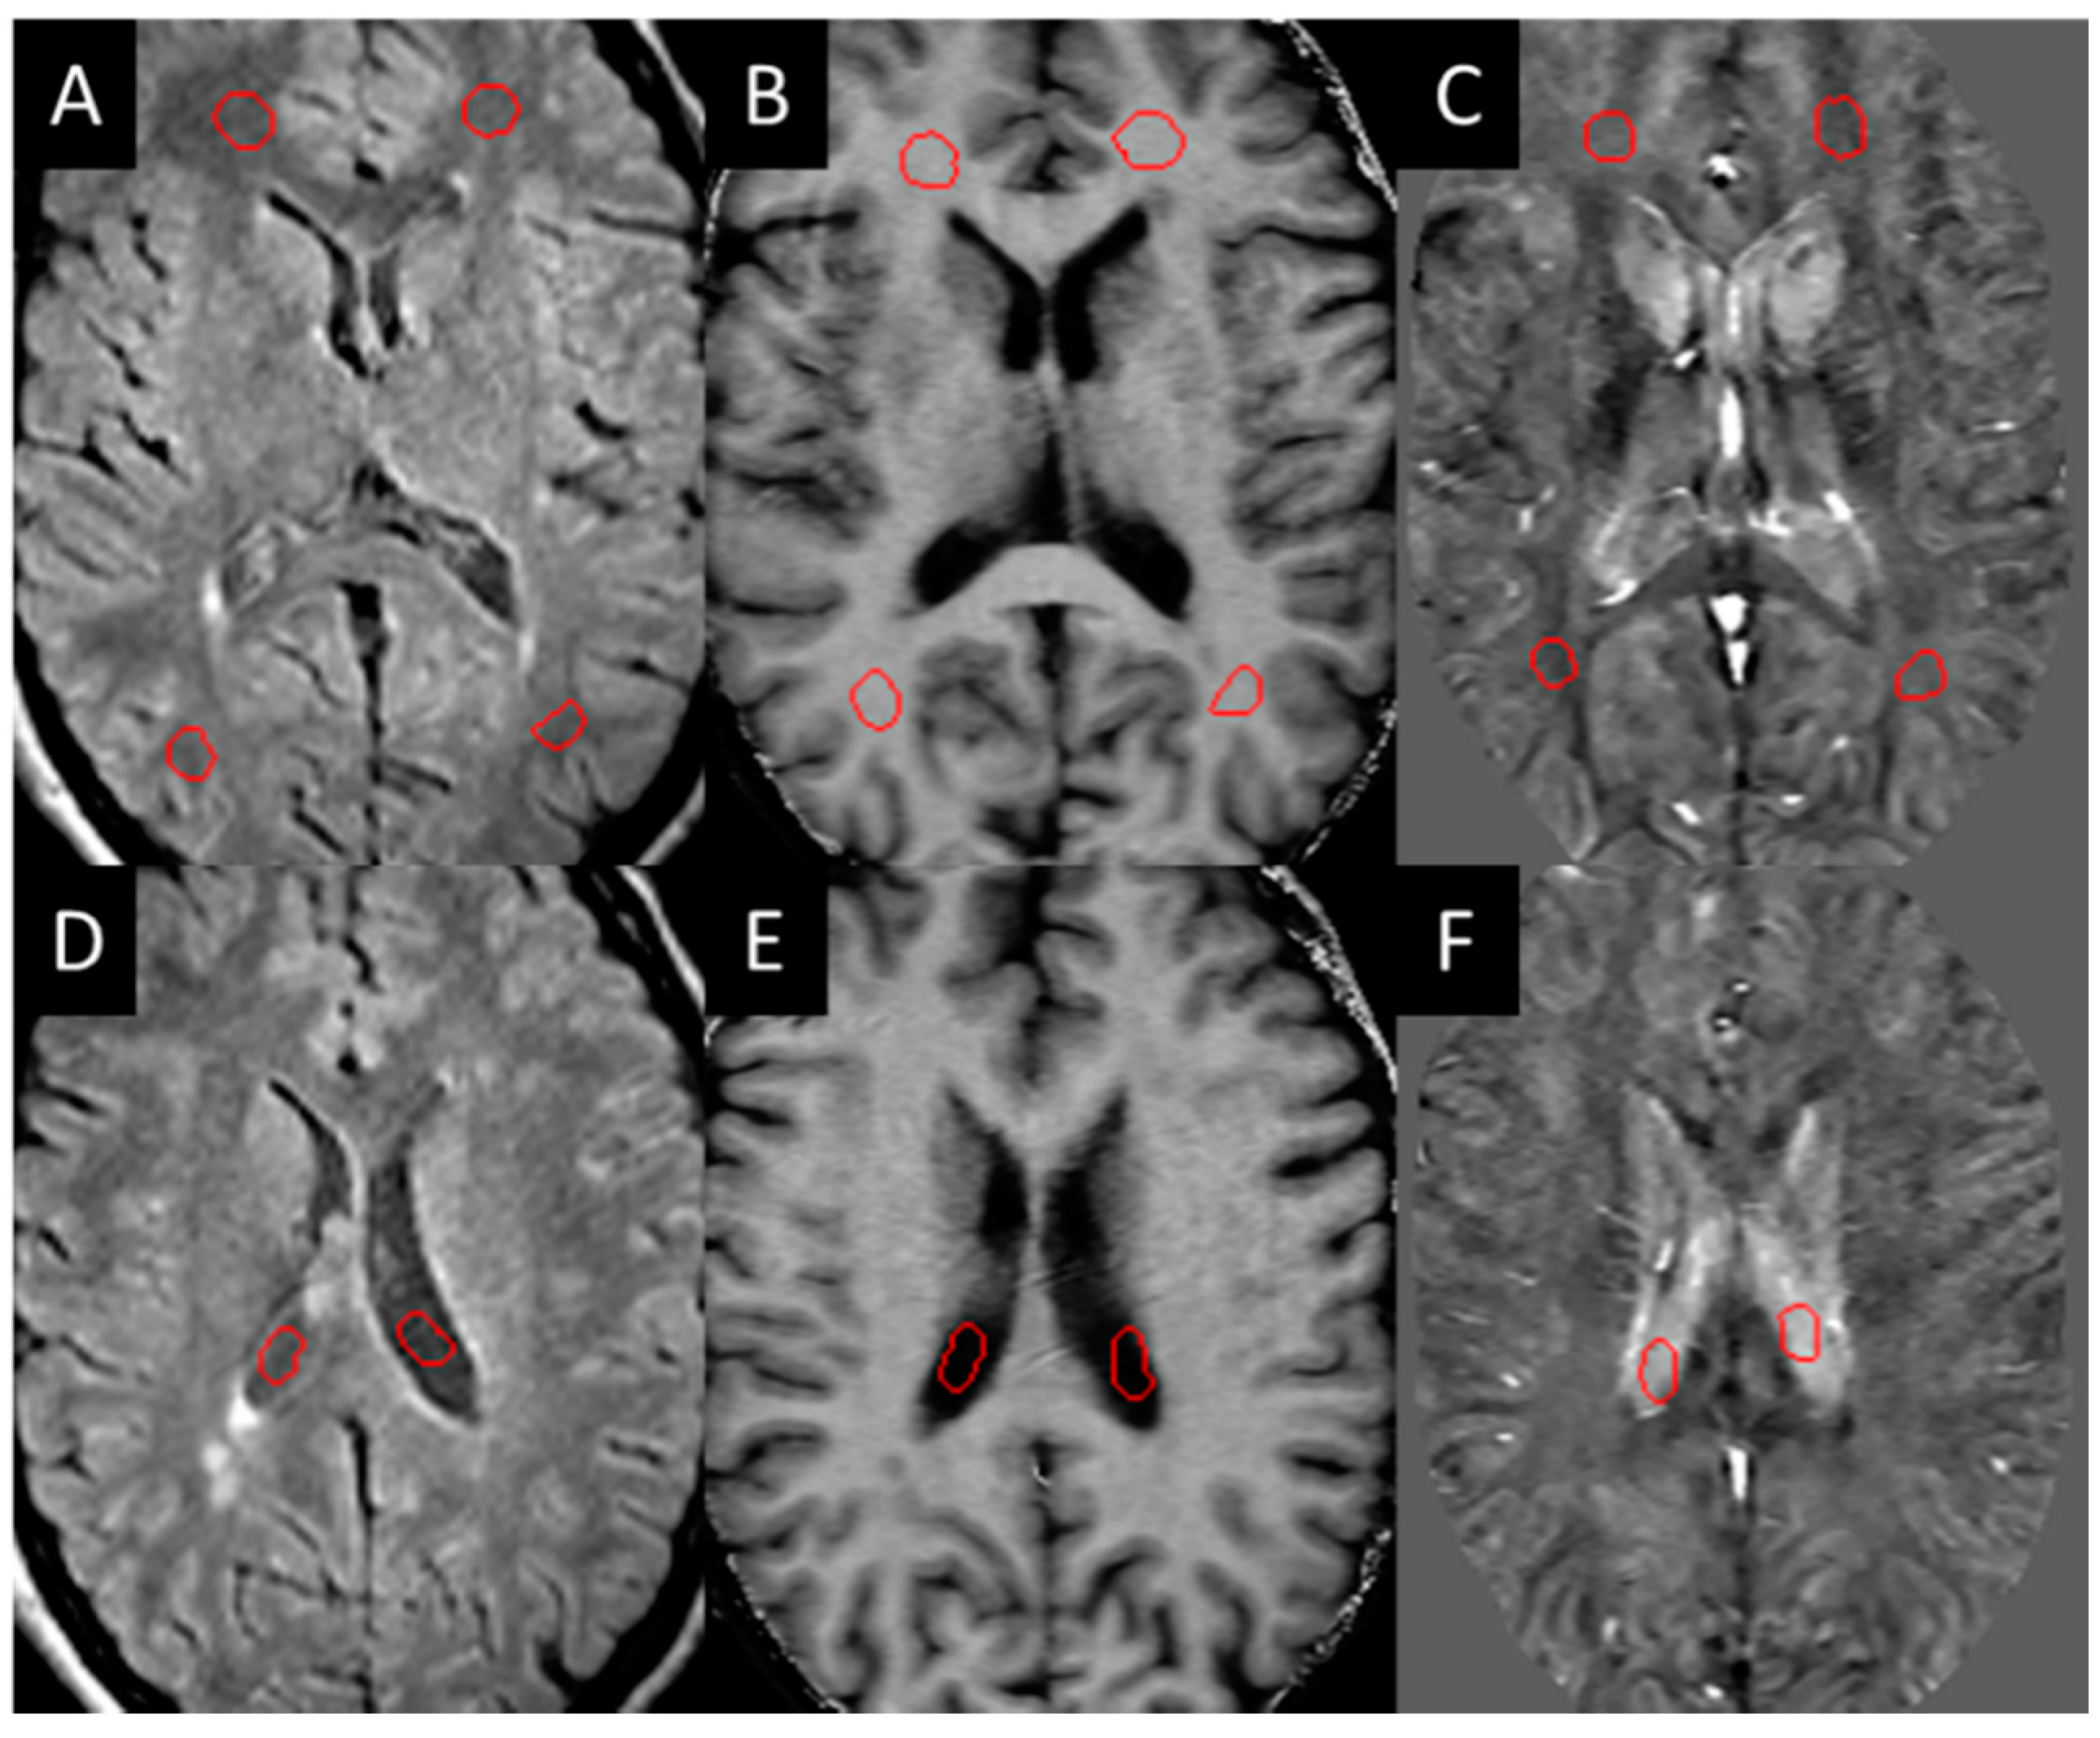

3.1. Lesions in MS Subjects

3.3. QSM ± Lesions